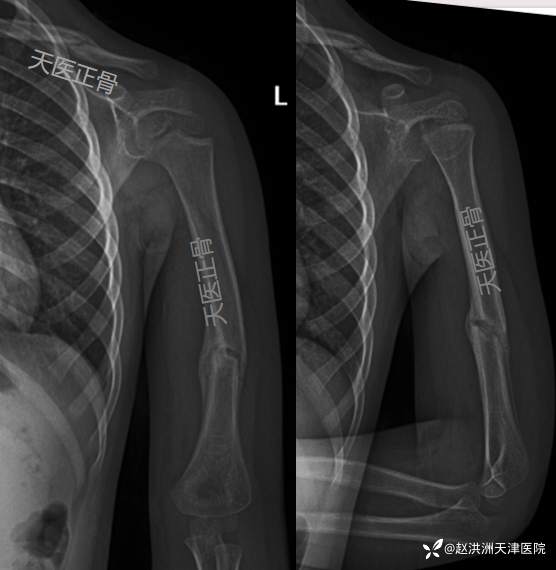

1周肱骨正位+穿胸位对位、对线同前

3周肱骨正位+穿胸位对位、对线可;断端可见骨痂,去除绷带

6周临床愈合良好,去除固定,肩肘关节功能锻炼